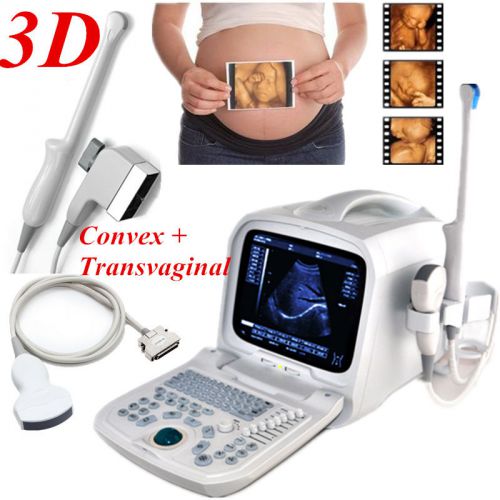

Internal 3D 3.5mhz convex+6.5mh Transvaginal Portable Ultrasound Scanner machine